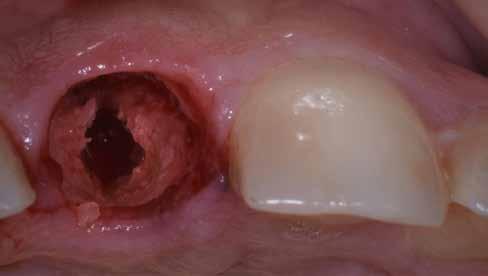

A 2020 januárjában elkezdett kezeléssorozat befejezését az év márciusában, hazánkba is begyűrűző Covid-19 pandémia késleltette, így kb. 6 hónap gyógyulás után láttunk hozzá az emergencia profil és a gingivális zenit ideiglenes koronával történő formázásához (11. és 12. kép). A 3 hetente végzett apró alakításokkal sikerült megfelelő ínyprofilt kialakítani, a „rózsaszín esztétika” a páciens számára is megfelelő volt. A bal felső nagymetsző fog meziális kompozit tömés cseréjét követően, individualizált nyitott kanalas lenyomati fejet készítettünk: az akrilát ideiglenes korona profilját átlátszó szilikonnal lemásoltuk, majd a körszimmetrikus gyári lenyomati fej és az ideiglenes korona kontúrja közötti hézagot folyékony kompozittal töltöttük ki (13. kép). Az így készített egyéni lenyomati fejjel vettünk lenyomatot a végleges, kerámialeplezésű cirkónium-dioxid vázas, átmenő csavaros rögzítésű koronához. (A fogtechnikai munkát Nébl Péter fogtechnikusmester készítette.), (14., 15., 16 és 17. képek).

A kész korona átadásakor a páciens elégedett volt az esztétikával, az azóta eltelt évben rendszeres kontrollokon jelent meg, melyek során meggyőződtünk a kemény- és lágyszövetek stabilitásáról (18. és 19. képek).